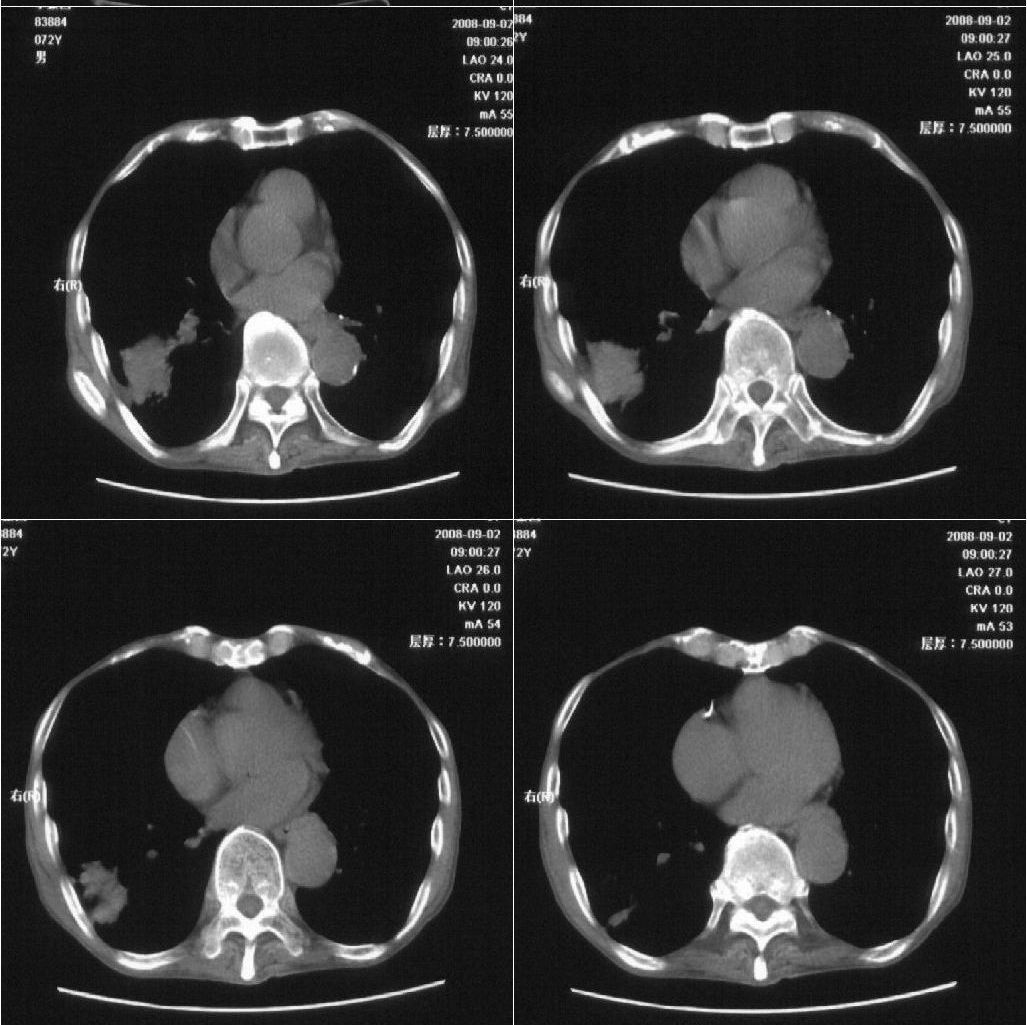

标题: CT15789:男性,72岁。食管癌术后14年。 [打印本页]

标题: CT15789:男性,72岁。食管癌术后14年。

痰培养:见葡萄球菌,霉菌少量生长。(此片系外院所作,仅提供了增强后的ct值为100hu,中心的坏死部分无强化,患者现在身体状况欠佳,为恶液质状态)

注意排外食管支气管瘘引起的肺部感染

符合机遇性感染,真菌可能性大。

该患者通过抗炎治疗明显好转:当时患者消瘦,实是因为患者进食量不多。患者有食道癌,因发生原发肺癌的机率并不高,当时的ct片除了增强感觉有强化外(其实这信息也并不确定,因为是外院ct),其实并没有发现支气管腔改变等直接征象。经过治疗,患者现在一般情况良好。以下是9月22日的复查片,发现病灶吸收明显。纵隔窗就不上传了。